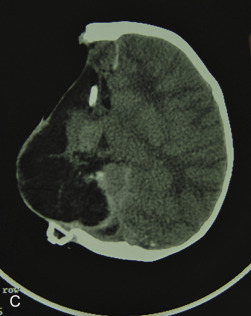

This 19-year-old male lost control of his bicycle on a wet bridge and was run over by a truck ( Fig. 3.1.2 ). After debridement of his compound right fronto-orbital defect, along with complete removal of the remnants of his frontal sinus (proper neurosurgical treatment), he was left with the defect shown, which was easily repaired with split calvarial bone from adjacent parietal bone.